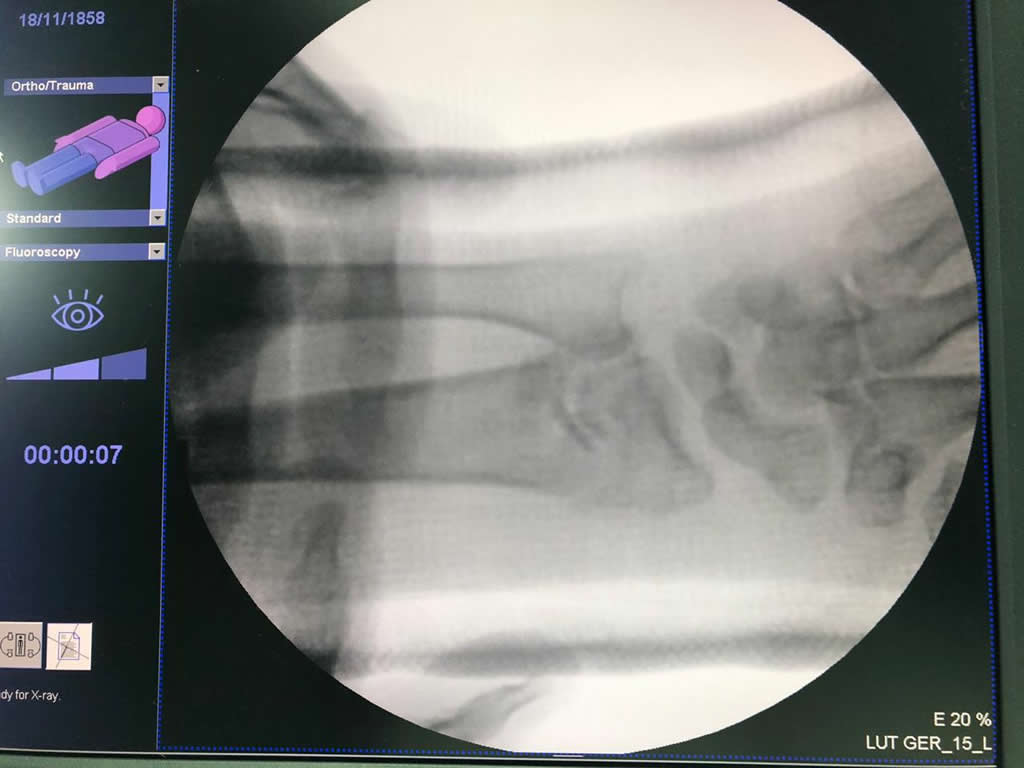

Cirugías de Calcaneo - Cirugías de Muñecas y Manos

Los procedimientos más comunes en cirugía de la mano son aquellos destinados a reparar traumatismos, incluyendo lesiones de tendones, nervios, vasos sanguíneos, y articulaciones; huesos fracturados; y quemaduras, cortes, y otros daños de la piel.